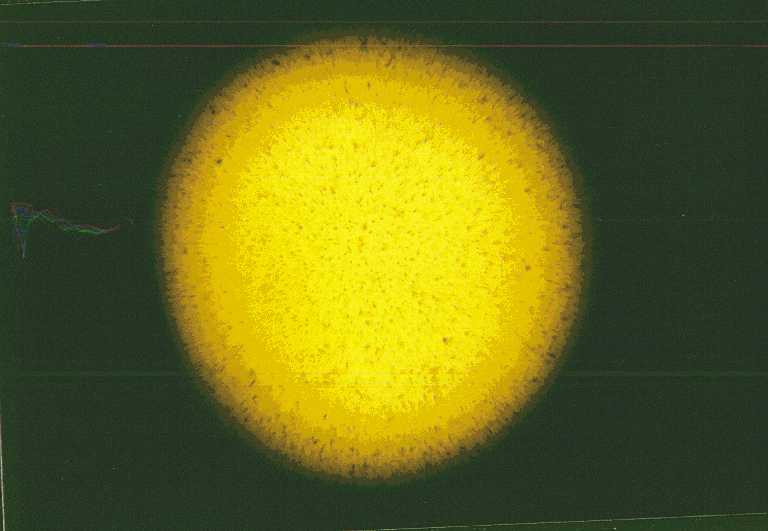

Bild 3: Typisches Schadensbild

einer altersgemäß verschlissenen und eingetrübtenOptik

(weil trübe) einzuschätzen ist. Des typische Bild des Inneren

einer einer trüben Optik zeigt Bild 3.